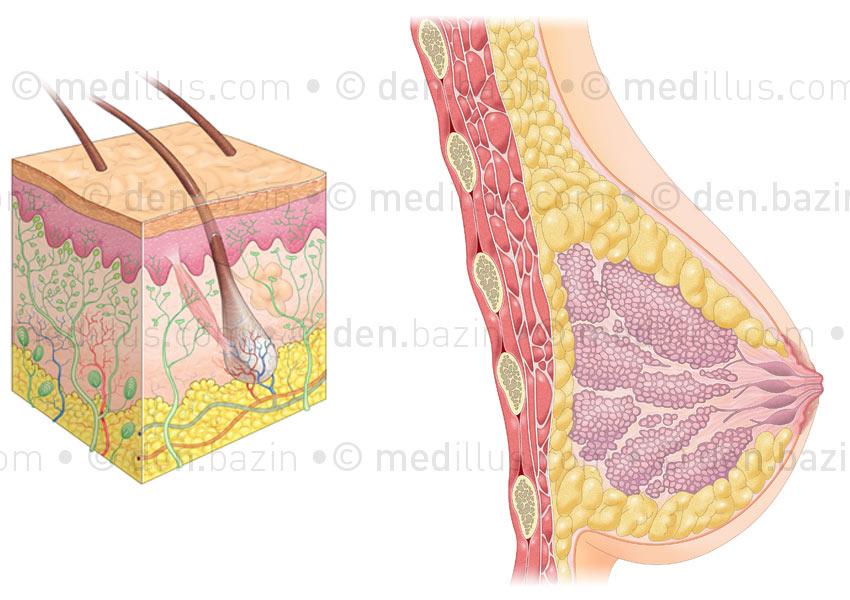

Coupe de peau et anatomie du sein